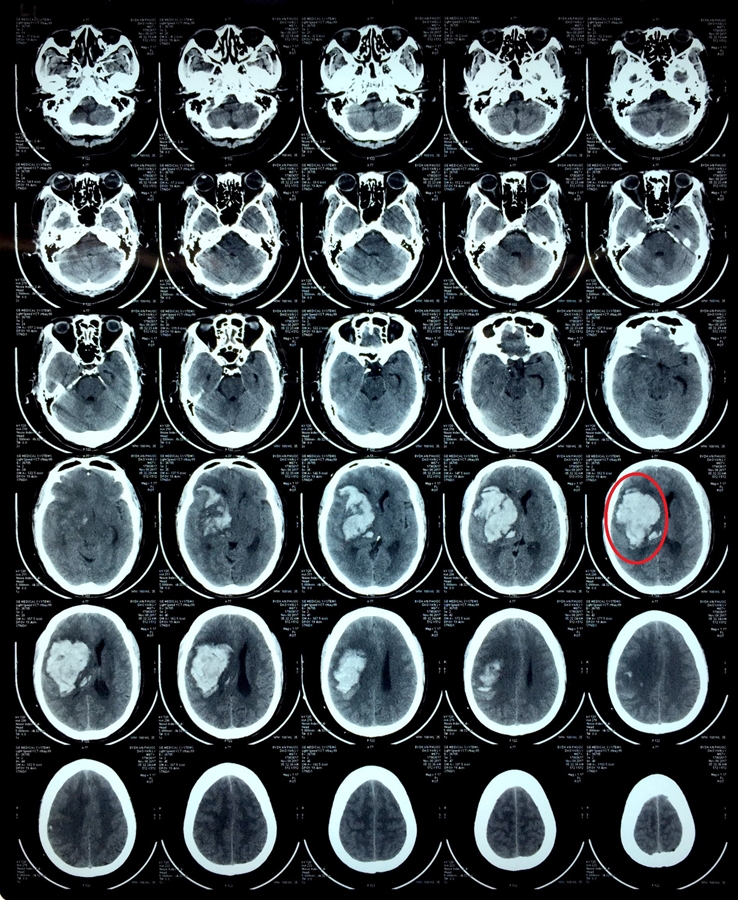

Hình ảnh chụp CT-Scanner sọ trước phẫu thuật

Vào lúc 5h15 ngày 8/11/2017, bệnh nhân nam ngụ tại Ma Lâm, Hàm Thuận Bắc được người nhà đưa vào viện trong tình trạng hôn mê, liệt nửa người bên trái, sinh hiệu: M 68 lần/phút, huyết áp 220/110, T 37,5 độ, NT: 20 lần/phút. Qua thăm khám, bệnh nhân được chẩn đoán ban đầu: Xuất huyết não bán cầu phải do tăng huyết áp. Bệnh nhân được chuyển vào khoa ICU - Hồi sức tích cực để điều trị và theo dõi diễn biến bệnh.

Đến 7h45 phút ngày 9/11, tập thể chuyên môn các bác sĩ đã hội chẩn, đặt ra chỉ định can thiệp phẫu thuật với chẩn đoán trước phẫu thuật: Xuất huyết não bán cầu phải/tăng huyết áp. Ca phẫu thuật được tiến hành trong khoản thời gian 3 giờ đồng hồ với êkíp phẫu thuật: Bs.CKII Lê Văn Anh và các đồng nghiệp, với phương pháp phẫu thuật mở nắp sọ lấy khoảng 60 gram máu tụ bán cầu phải.